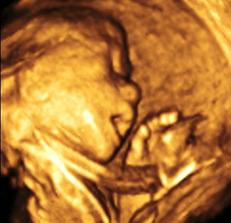

Ako nám to ide...